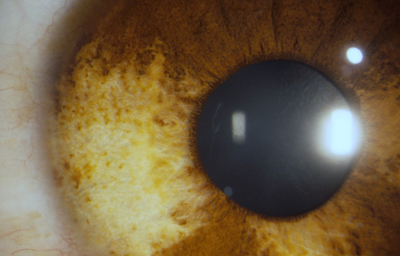

El Color del Iris

El Iris en general es muy pigmentado con colores que comúnmente van del marrón, avellana, gris, verde y azul. Existen los iris sin pigmento en el Albinismo oculo-cutáneo en cuyo caso se ven blanco/rosados.

El color del Iris es un fenómeno complejo por efectos combinados por la textura, la pigmentación y el tejido fibrovascular del estroma, junto con la constitución epigenética del individuo. Desde el punto de vista óptico, la simple absorción o reflexión selectiva por algunas moléculas, como la hemoglobina o el colágeno del estroma que son componentes no pigmentados, puede tener influencia en el color que es observado.

A pesar de la gran variedad en el color del Iris, el único pigmento que contribuye en forma sustancial es la melanina; su cantidad, es uno de los factores que determina el color del iris en una persona. Estructuralmente el color depende de la cantidad variable de eumelanina (melaninas marron/negra) y pheomelanina (melaninas rojo/amarillo) producidas por los melanocitos derivados de la Cresta Neural. El grado de dispersión de la melanina que yace en racimos subcelulares en los melanosomas, tiene cierta influencia en el color que se observa, pero el grado de dispersión no es reversible ya que los melanosomas no son moviles.